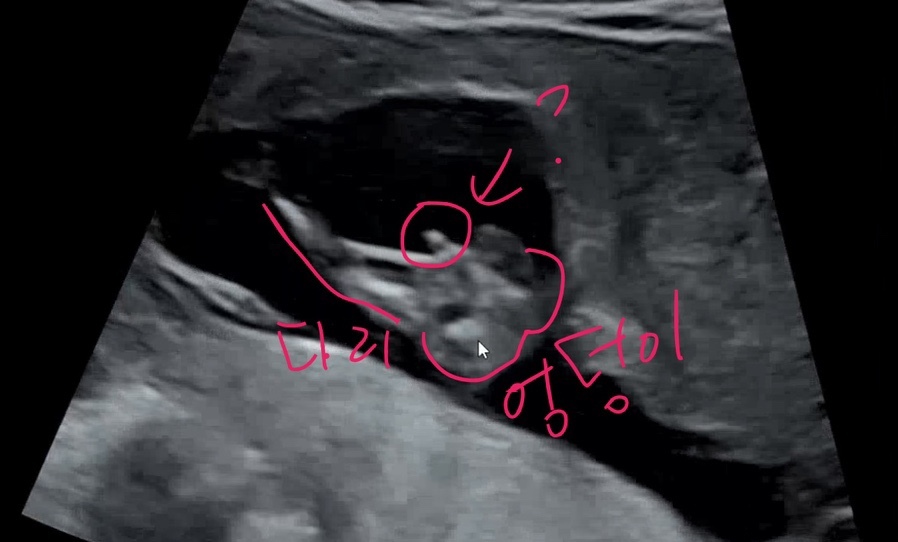

그렇다면 한번 다른 방법인 삼각점을 살펴보자!

초음파 삼각점이란?

다리 사이를 본 초음파에 남성의 성기 중 하나인 *추와 fire egg가 살짝 보이는 삼각점으로 남자아이인지 맞춰보는 것. 여자아이의 경우는 튀어나와 있어도 이 삼각점이 있지 않다~는!

보통 어떤 분들의 영상에는 정말 삼각점이 뙇하고 보이는 경우도 있는데 나는 이것도 약간 불확실한 너낌.

삼각점이 보이시나요?

삼각형이 점!+점! 으로 보이면 조금 더 확실할텐데 아들로 보이긴 하지만 아들이 확실하진 않은 듯하다. ㅜ